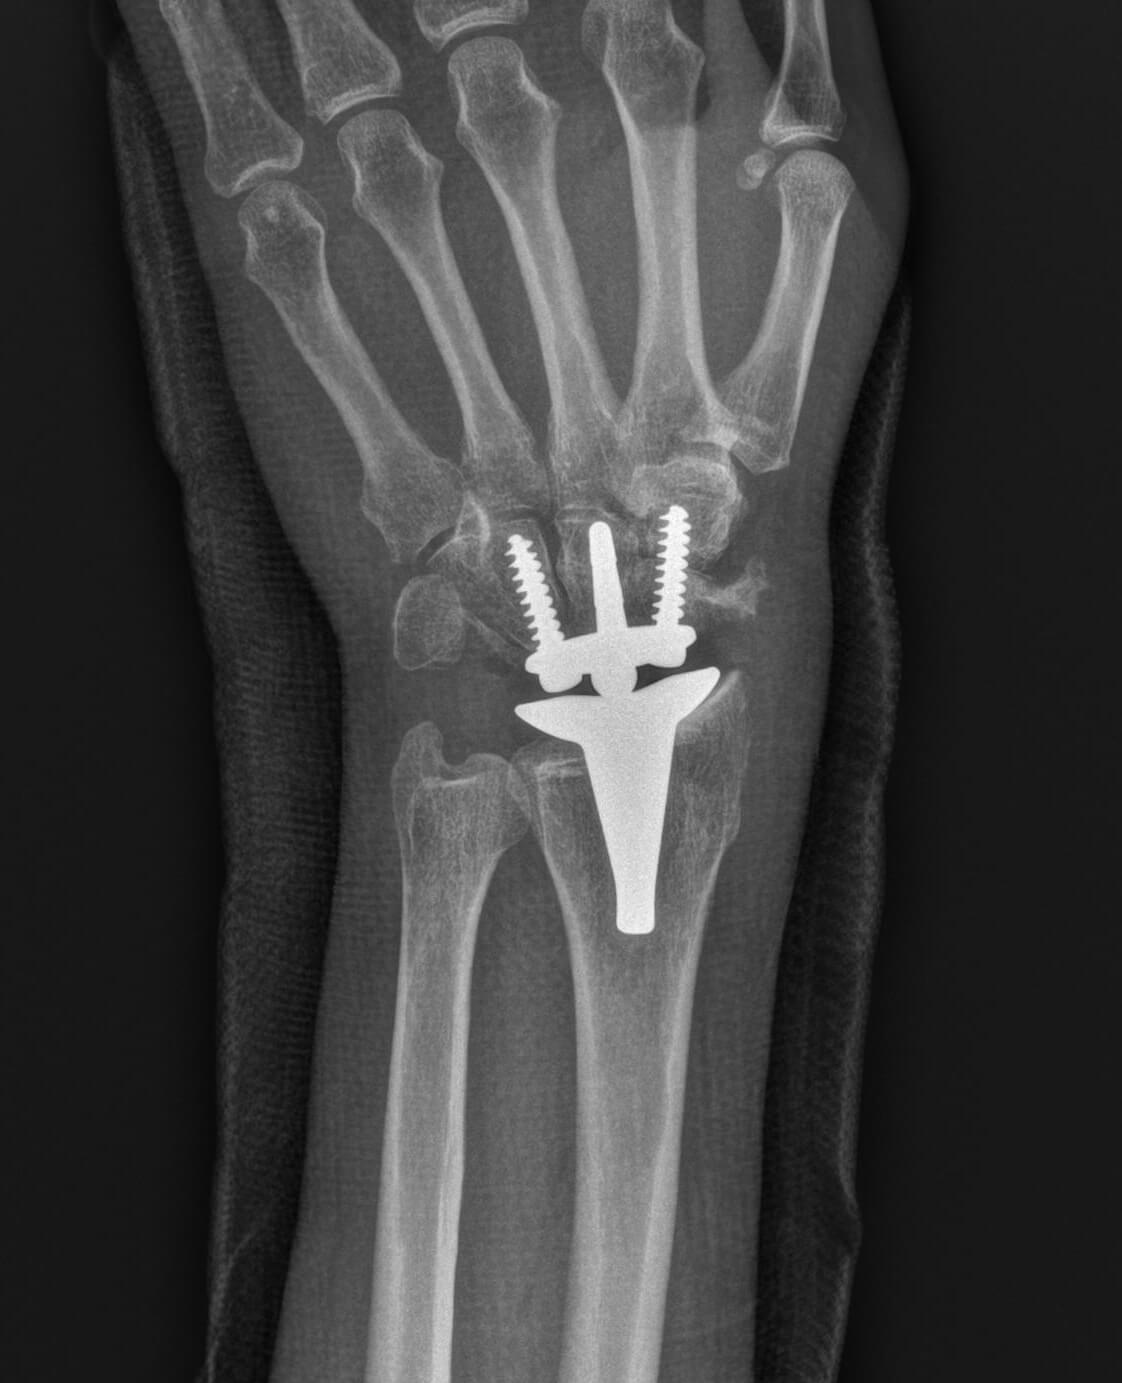

Seit meiner Ausbildung widme ich mich in meiner Arbeit und Forschung intensiv der Handchirurgie. Somit kann ich Ihnen das gesamte Spektrum der konservativen und operativen Behandlung von Hand- und Unterarmerkrankungen anbieten. Als Unfallchirurg habe ich mich auf die Versorgung von handnahen Verletzungen spezialisiert. Als Orthopäde widme ich mich der Versorgung von abnützungsbedingten Erkrankungen der Gelenke sowie Sehnen- und Nervenerkrankungen.